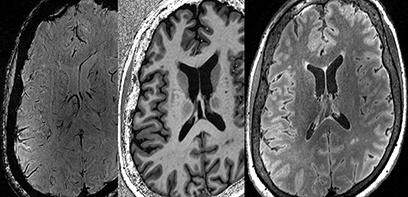

New study expands understanding of brain blood flow and neurological disorders

March 07, 2024

Researchers developed an efficient non-invasive method map blood flow (perfusion) in the hippocampus at an unprecedented resolution.